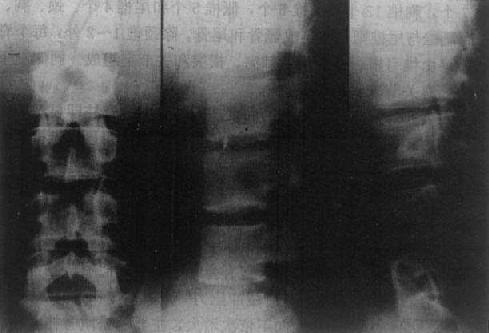

图2-1-5 正常腰椎正侧位

图2-1-6 正常腰椎(正位、侧位、斜位)

在正位片上,椎体呈长方形,从上向下依次增大,主要由松质骨构成,纵行骨小梁比横行骨小梁明显,周围为一层致密的骨皮质,密度均匀,轮廓光滑。椎体两侧有横突影。在横突内侧可见椭圆形环状致密影,为椎弓根横断面影像,称椎弓环。在椎弓根的上下方为上下关节突的影像。椎弓板由椎弓由椎弓向后内延续,于中线联合成棘突,投影于椎体中央的偏下方,呈尖向上类三角形的线状致密影,大小与形状不同(图2-1-5、6)。

在侧位片上,椎体也呈长方形,其上下缘与后缘成直角。椎弓居其后方。在椎体后方的椎管显示为纵行的半透明区。椎弓板位于椎弓根与棘突之间。棘突在上胸段斜向后下方,不易观察,于腰段则向后突,易于显示。上下节突分别起于椎弓根与弓板连接之上、下方,下关节突在下个脊椎上关节突的后方,以保持脊椎的稳定,不向前滑。脊椎小关节间隙匀称的半透明影。颈、胸椎小关节侧位清楚,腰椎正位清楚。椎间盘的纤维软骨板、髓核及周围的纤维环系软组织密度,故呈宽度匀称的横行半透明影,称之为椎间隙(intervertebral space)。椎间孔居相邻椎弓、椎体、关节突及椎间盘之间,呈半透明影,颈椎斜位显示清楚,胸、腰椎侧位清楚,呈类圆形(图2-1-5、6)。